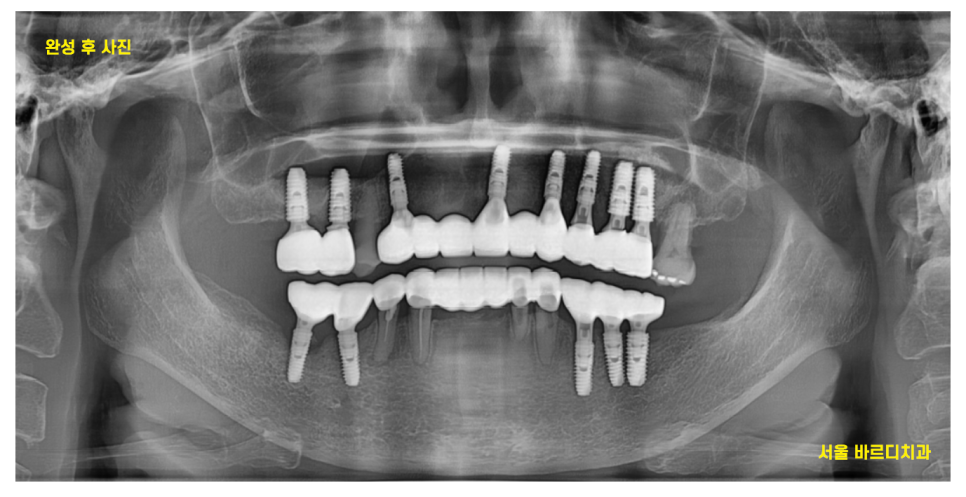

24.04.30

최대한 암사동 치과 내원 횟수를

줄일 수 있게

진행해드렸었는데요.

긴 시간동안 진료에

협조해주셔서 감사합니다 환자분

디지털 장비를 사용한 꼼꼼한 분석으로

전악 임플란트 하루만에 끝낼 수 있습니다.